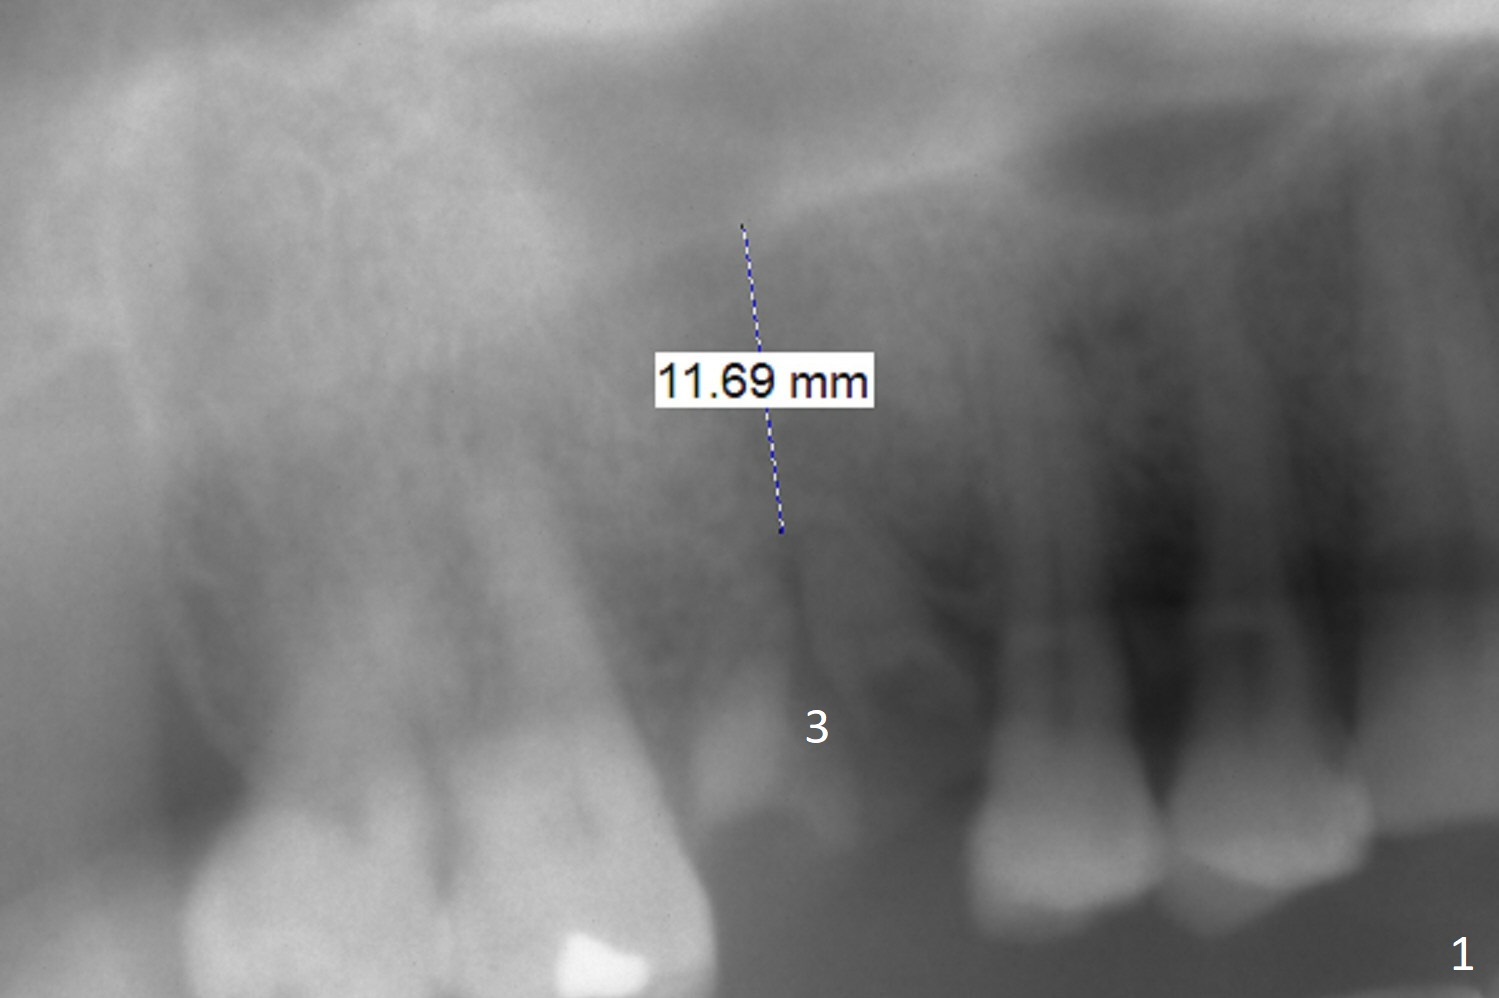

A 59-year-old man had #29 and 30 implants placed at the same time.  At stage of restoration, there is insufficient clearance between #30 abutment and #3 residual roots.  One month post #29 crown cementation, the patient will return for #3 implant placement.  To get enough clearance, the implant and abutment at #3 seem necessary to be placed as high as possible, while the abutment cuff and length at #30 need to be decreased.  To reduce sinus membrane perforation, control osteotomy depth precisely (Fig.1).  Take preop photo to show the insufficient occlusal clearance.